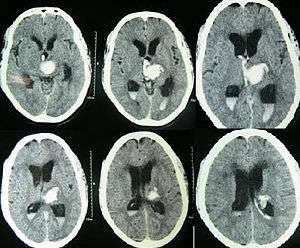

| CT scan of a spontaneous intracerebral bleed, leaking into the lateral ventricles | |

Both computed tomography angiography (CTA) and magnetic resonance angiography (MRA) have been proved to be effective in diagnosing intracranial vascular malformations after ICH.[13] So frequently, a CT angiogram will be performed in order to exclude a secondary cause of hemorrhage[14] or to detect a "spot sign".

Intraparenchymal hemorrhage can be recognized on CT scans because blood appears brighter than other tissue and is separated from the inner table of the skull by brain tissue. The tissue surrounding a bleed is often less dense than the rest of the brain because of edema, and therefore shows up darker on the CT scan.[14]